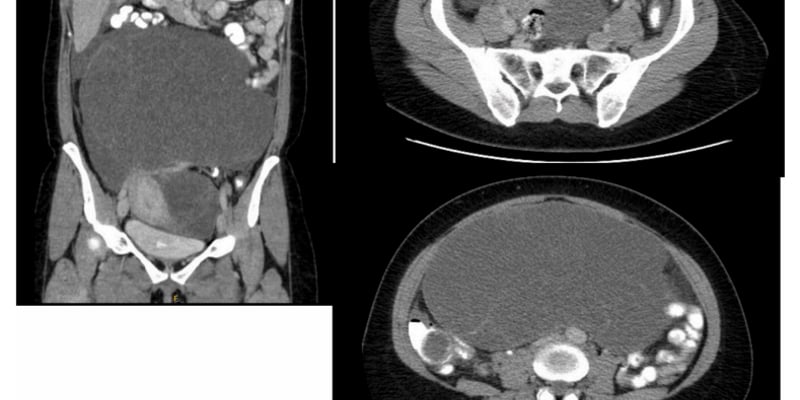

使用携带致癌基因的捐精者的精子,成功孕育了近200名儿童(图源:BBC新闻)

- 腹部/盆腔超声检查: 每3至4个月进行一次。用于筛查肾上腺皮质癌、肾脏肿瘤等。

图源:EUROVISIO News